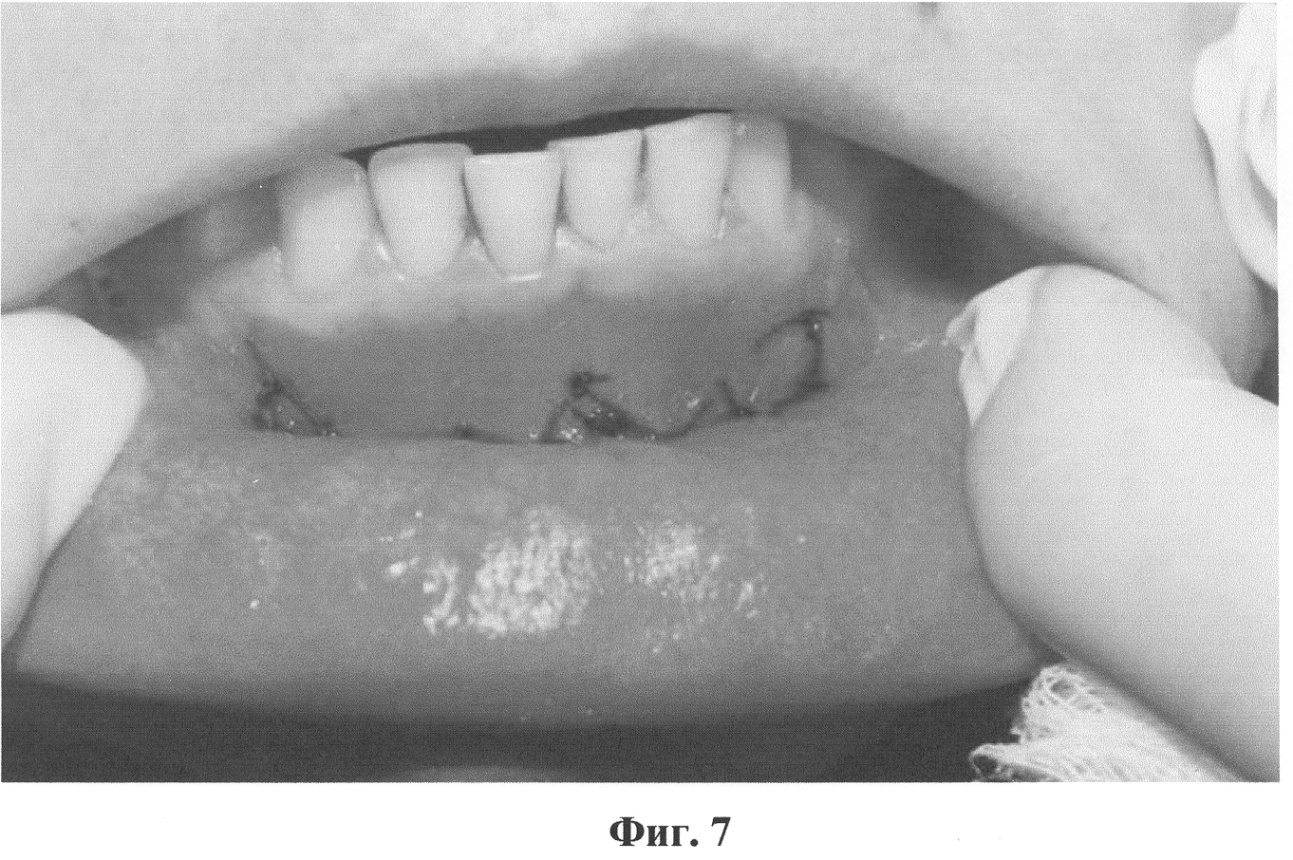

Фиг.7. Состояние после фиксации слизистой оболочки к надкостнице и ушивания ран.

После курса противовоспалительной терапии проведена вестибулопластика на нижней челюсти по предлагаемому способу. На фото (фиг.5) показана полость рта пациентки с мелким преддверием до операции. Под инфильтрационной анестезией сделаны разрезы слизистой оболочки преддверия полости рта в вдоль уздечки нижней губы и слизистых тяжей на всю их длину между 33 и 34, 43 и 44 зубами. Тупо отслоены подслизистые ткани вдоль надкостницы на запланированную глубину преддверия, определено отсутствие тяжей и мышечных волокон (фиг.6). Мобилизованная слизистая оболочка подшита к надкостнице на глубине 12 мм резорбируемым шовным материалом (Dexon), вертикальные разрезы ушиты также с фиксацией к надкостнице на необходимой глубине (фиг.7).

Пациентка отмечала болевой синдром в течение 8 часов после операции, на следующие сутки после операции выявлена незначительная отечность мягких тканей нижней губы. Швы сняты на 6 сутки после операции.